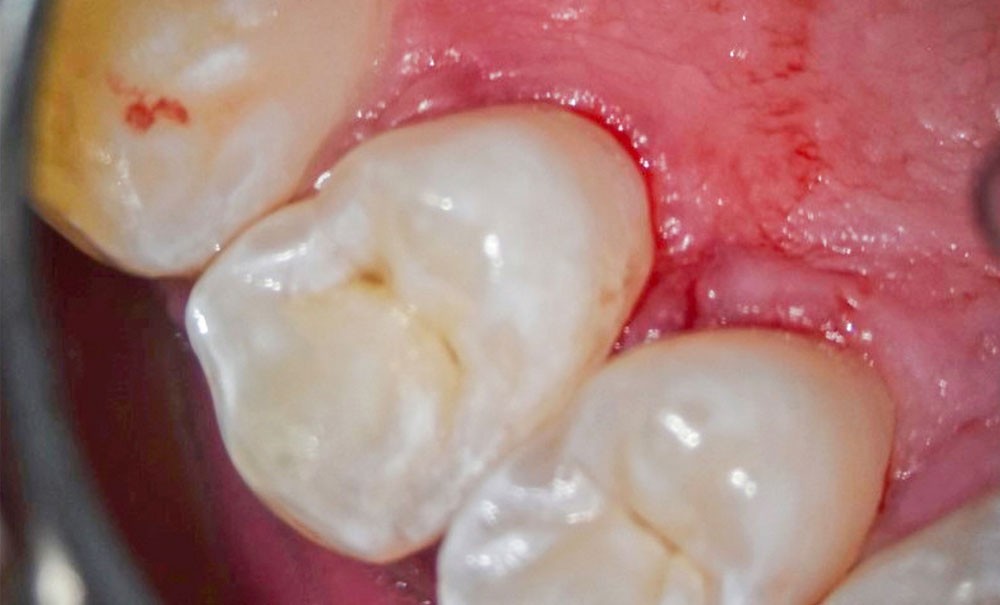

L’objectif de cet article est de discuter l’utilisation des matériaux bioactifs ou bio-interactifs libérant des ions (MBA ou IRB) dans la prise en charge opératoire invasive des lésions carieuses modérées à extensives occlusales et proximales (ICDAS 3-4, 5-6) et d’introduire le Bioactif Dental Concept (fig. 1).

Critères d’intervention pour les lésions extensives couplés aux matériaux bioactifs

Trois critères s’imposent : la présence d’une cavitation, l’activité carieuse et l’absence d’émail cervical [3].

L’utilisation des MBA (lésions occlusales ou proximales) doit être privilégiée dans ces situations cliniques selon le concept bioactif :

• patient à haut risque carieux : les lésions carieuses seront restaurées en totalité aux ciments verres ionomères haute viscosité (CVI-HV) de préférence ou avec un mineral enriched composite de type Cention®, Activa® et Surfil® One en attendant la stabilisation du risque carieux ou si les conditions parodontales ne sont pas favorables à des restaurations d’usage ;

• lésion dentinaire active : pour favoriser une réversion carieuse, bénéficier d’un effet tampon du matériau et, dans la zone d’inter-diffusion, d’espérer un potentiel de reminéralisation ;

• lésion proximale sans émail cervical, sans compter l’activité carieuse [4].